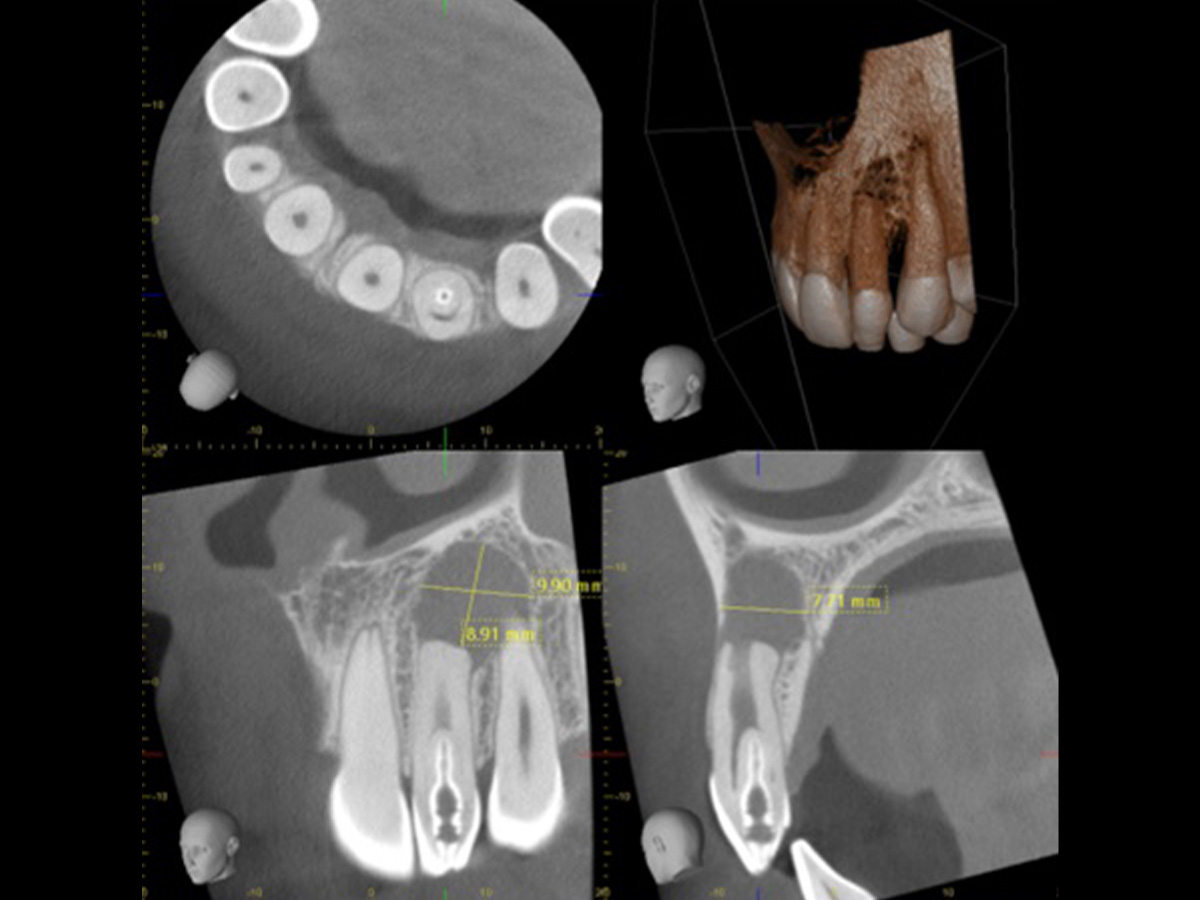

Viele Zahnärzte nutzen die Digitale Volumentomografie (DVT) im Alltag nicht, da ihnen die grundlegenden Kenntnisse über diese Technik fehlen. An den Universitäten werden die endodontischen Konzepte häufig nur anhand von Einzelbildern vermittelt, weshalb in der Praxis das notwendige Wissen fehlt, um diese Technologie sinnvoll am Patienten einzusetzen. Erlernen Sie in praktischen Übungen am Computer, wie die DigitaleVolumentomografie (DVT) die endodontische Diagnostik und Behandlung beeinflusst. „Der Behandlungsplan ändert sich in etwa 50 % der Fälle, nachdem der Behandler eine DVT beurteilt hat“ (Rodriguez et al., Journal of Endodontics, 2015: Influence of Cone-beam Computed Tomography on Endodontic Retreatment Strategies among General Practitioners and Endodontists).Aus diesem Grund gewinnt diese Technik zunehmend an Bedeutung. Erfahren Sie mehr über die Vorteile dieser diagnostischen Methode, ihre Indikationen und Anwendungen. Unterstützt von der Carestream CS 3D Imaging Software analysieren Sie Schritt für Schritt verschiedene Fälle und erstellen eine präzise Diagnose sowie eine fundierte Therapieplanung.